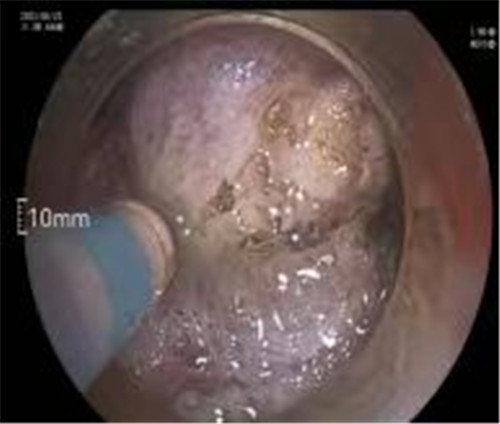

近期病例之一,圖片依次為:胃鏡、超聲胃鏡、ESE術(shù)中、術(shù)后、切下病變。

通過(guò)內(nèi)鏡切開(kāi)瘤體表面粘膜,分離后挖除瘤體,或以消化道全層切除的方法切除瘤體,并在內(nèi)鏡下縫合切口。與傳統(tǒng)手術(shù)相比,該項(xiàng)技術(shù)利用了人體自然通道,不會(huì)破壞人體結(jié)構(gòu),更加微創(chuàng)。不超過(guò)3cm向消化道腔內(nèi)生長(zhǎng)為主的良性或低度惡性粘膜下腫瘤(如間質(zhì)瘤、類癌、平滑肌瘤等),都可采用ESE治療。